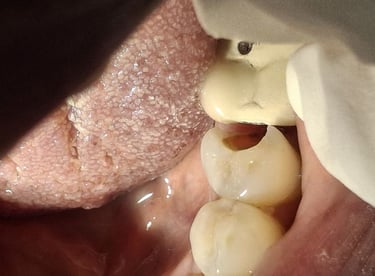

Root Canal Treatment near Shyamal, Ahmedabad

Before

After

All images shown here represent real clinical cases treated at our dental clinic with patient consent.

At Shree Dental Care, we focus on gentle, precise, and well-planned root canal treatment to remove infection, relieve pain, and preserve your natural tooth structure.

Patients from Shyamal and nearby areas of Ahmedabad visit our clinic for comfortable root canal procedures carried out using modern techniques and strict hygiene protocols. The treatment helps eliminate infection from inside the tooth, prevents further damage, and restores normal chewing function.